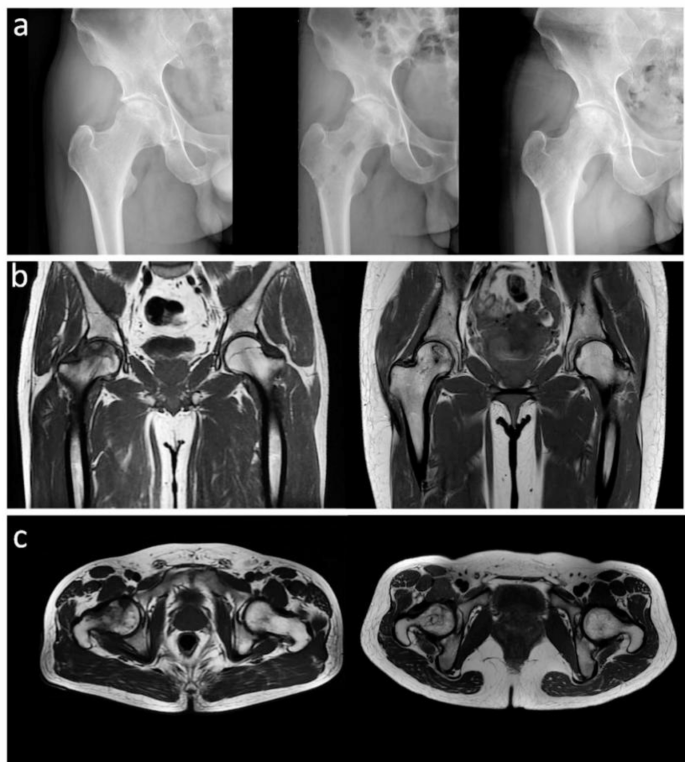

There was no significant difference in Harris score between the two groups at 1 week after operation (74 ± 5.3 vs. 73 ± 6.6, p > 0.05). However, at 3, 6, 9 and 12 months after operation, the Harris hip score of the new method group was higher than that of the traditional method group (p < 0.05) (Table 2). As shown in Table 2, the Harris scores of the two groups showed a gradual upward trend during the postoperative follow-up, and the new device method group was more obvious than the traditional method group. The pain symptoms of the new device method group were relieved and the VAS score was lower, and the difference was statistically significant compared with the traditional method group (p < 0.01) (Table 3). The VAS scores of the two groups showed a gradual downward trend during the postoperative follow-up, and the new device method group was more obvious than the traditional method group (Table 3). There were no associated complications such as delayed wound healing, infection, fracture, instrument trouble, nerve injury and vascular injury in the new method group. There were no infection, fracture and other complications in the traditional group, but one patient had delayed wound healing. As shown in Fig. 6, at 3 months after core decompression, X-ray showed that the bone tunnel was partially filled with bone in the new device method group, all the bone tunnels were filled with bone by 9 months after operation, and MRI showed that the area of femoral head necrosis was less than that before operation at 9 months after operation.